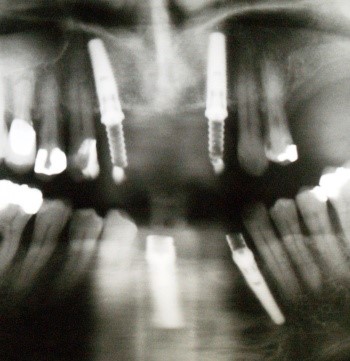

На фото представлены все этапы имплантации зубов от исходного состояния пациента до конечного результата.

На фото обычный случай замены одного зуба имплантатом, а также решение в случае беззубой челюсти или челюсти, пораженной пародонтозом.

Имплантация в стоматологии «Аркобалено» при пародонтозе зубов, представлены все этапы имплантации под ключ.